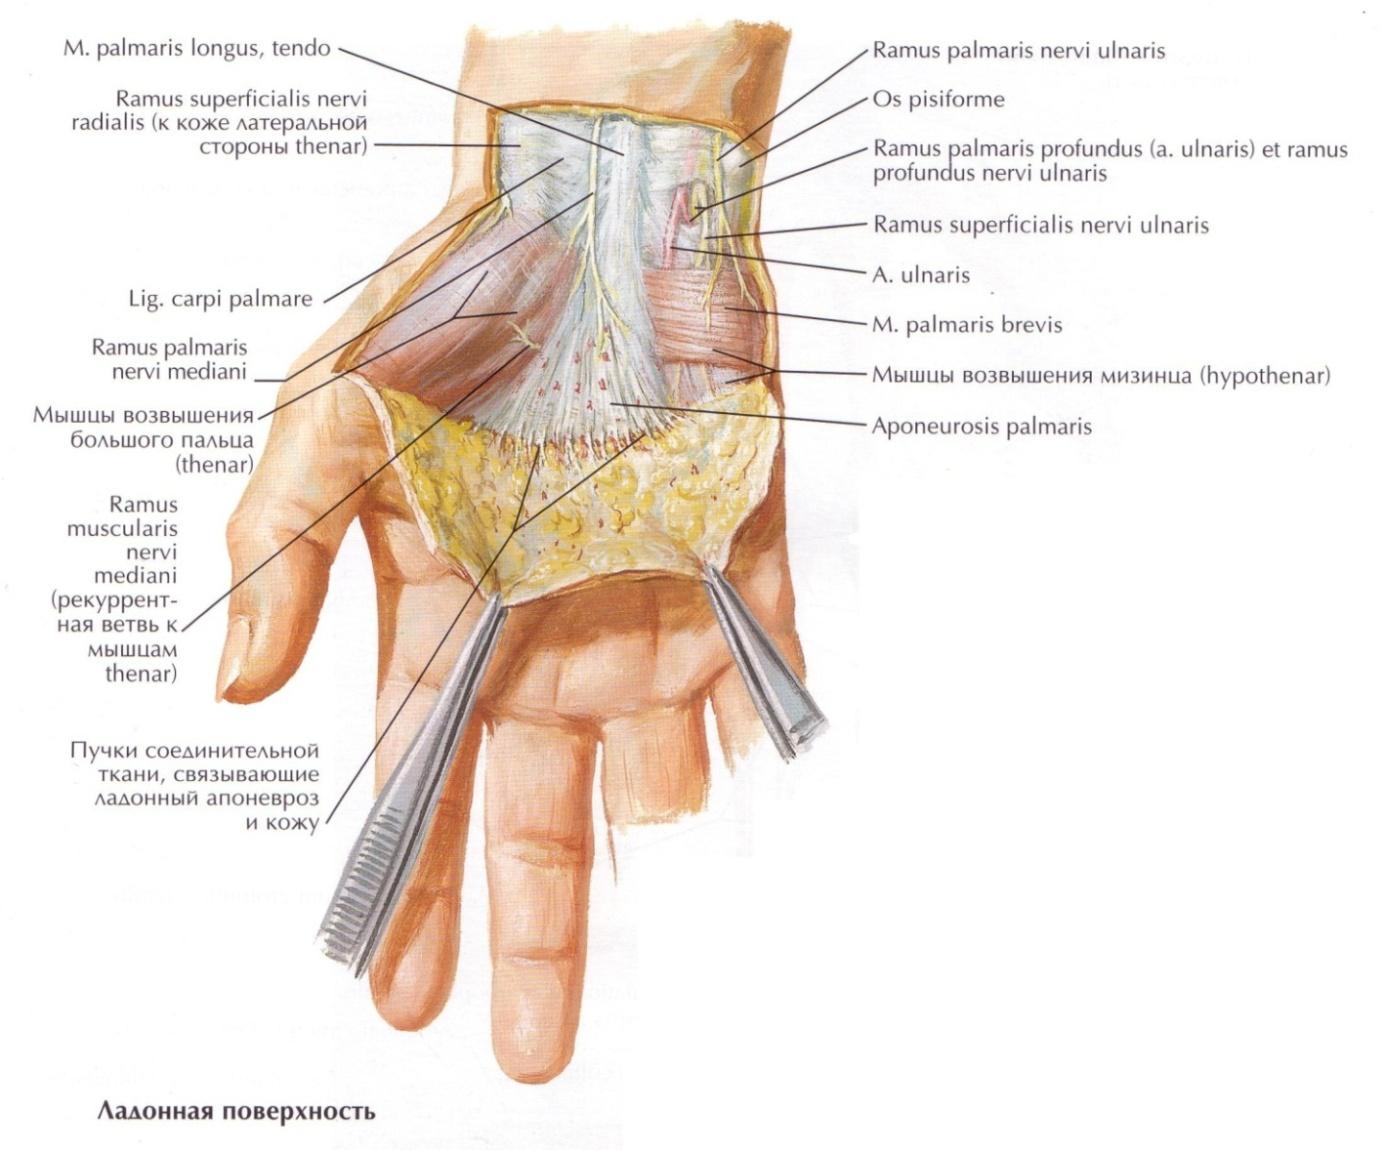

Анатомия мышцы Palmaris Longus

Раздел: Иллюстрированный журнал